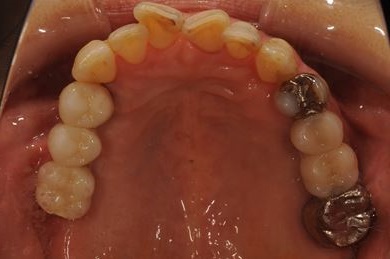

インプラントの症例写真 IMPLANT

骨再生インプラント治療

| 性別/年齢 | 女性 / 51歳 | ||||||||||||||||||||||||||||||||

| 主訴 | 他の歯科医院で入れ歯を入れたが、滑舌や味などで不自由を感じている。インプラントは難しいと言われたが、可能かどうかみていただきたい。 | ||||||||||||||||||||||||||||||||

| 治療方針 | サイナスリフトにより上顎洞を拳上し、インプラント治療を可能にする。 | ||||||||||||||||||||||||||||||||

| 治療内容 | インプラント3本(サイナスリフト)、ハイブリッドセラミッククラウン5本 | ||||||||||||||||||||||||||||||||

| 総治療費 | 2,111,813円 | ||||||||||||||||||||||||||||||||

| 治療期間 | 1年3ヶ月 |